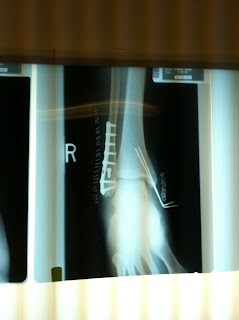

In the process of crashing my foot stayed attached to the pedal (with my lovely Egg Beater pedals) while my leg began to rotate around it. When I finally stopped I found that my foot was pretty much dangling from the rest of my leg. When I started to move my leg, the foot just stayed in place. The next photo is of the first x-ray I decided to take a picture of. Obviously this is a picture of my foot after surgery.

I ended up with what they call a 'Trimalleolar Ankle Fracture'. Yes I was sort of like what is that. Well I came to find out that its a combination of three broken (tri) bones in my ankle. I already knew what had happened was no good. I mean when your foot (or any other part of your body for that matter) is simply dangling from your leg, you know its pretty bad. You can search the type of break and get a multitude of views and opinions if you like, but this image that I found sort of shows it in its best viewable way: